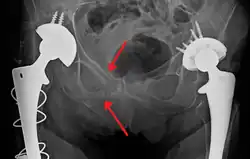

| A pelvic X-ray showing an open book fracture | |

Open book fracture

One specific kind of pelvic fracture is known as an 'open book' fracture. This is often the result of a heavy impact to the groin (pubis), a common motorcycling accident injury. In this kind of injury, the left and right halves of the pelvis are separated at front and rear, the front opening more than the rear, i.e. like an open book that falls to the ground and splits in the middle. Depending on the severity, this may require surgical reconstruction before rehabilitation.[12] Forces from an anterior or posterior direction, like head-on car accidents, usually cause external rotation of the hemipelvis, an “open-book” injury. Open fractures have an increased risk of infection and hemorrhaging from vessel injury, leading to higher mortality.[13]